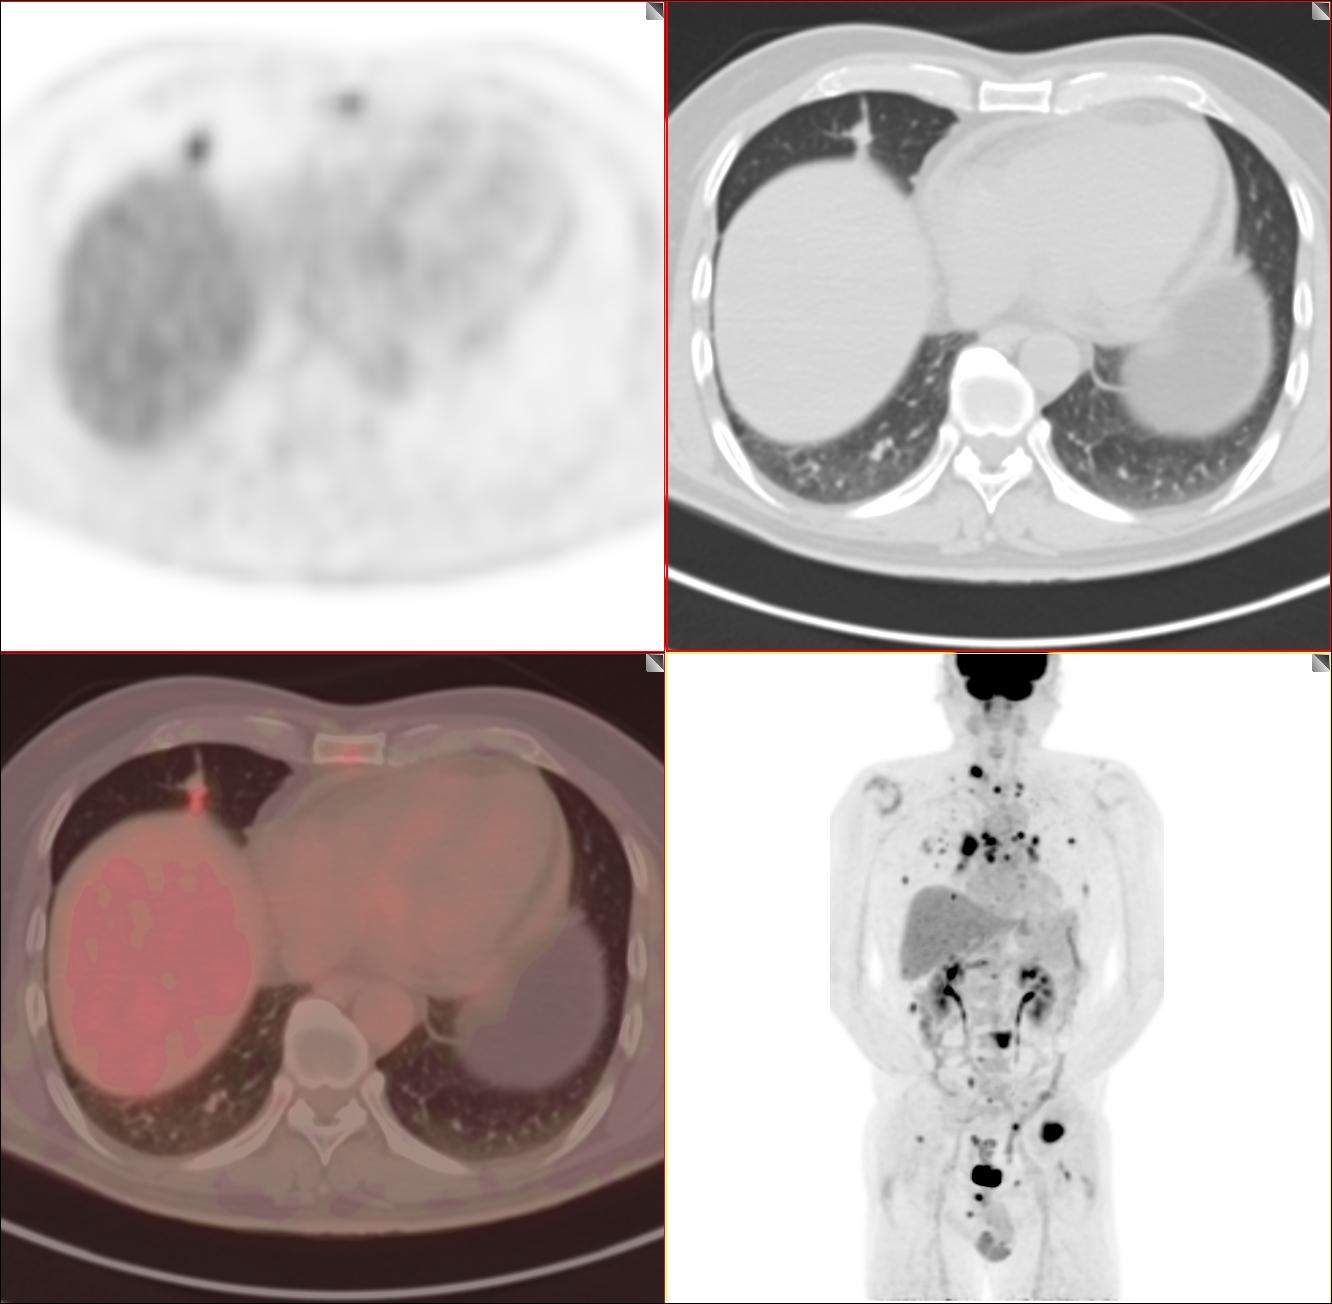

原因是这么一回事,遇到1例肺结节患者,病灶最大直径约1.5cm结节,结果转移得一塌糊涂!双肺弥漫性转移(肺内多达几百个病灶)、全身多发骨转移、全身多发淋巴结转移。

就是这么一个小病灶。为了不引起大家不适,我不发更多的图片

患者仅有50多岁,巫医生的心就落到了谷底。追寻病史,患者间隔1年没有体检,就成了现在的这个状况,肺癌四期。趋势这个实性的病灶有点大,如果再1cm以内做一个检查,相信不会发生这么严重的转移。

大部分这一类病灶爆发大概就是几个月的时间,巫医生替这位患者感到惋惜,50多岁应该每年体检一次,陪着患者来就诊的是一位外地的地级市,市医院的普外科主任,他也很惋惜,虽然不知道是什么关系,但也能看到他的痛心疾首。

巫医生整天的心情都不好,从做科普以来,感觉心和每一位患者的疾痛都交织在一起,我也很痛,今天也感觉很累。现在也只能祈祷了,这个病灶腺癌的可能性非常大,腺癌靶向治疗效果还不错。如果靶向药物能匹配上,也许还会有控制的机会。